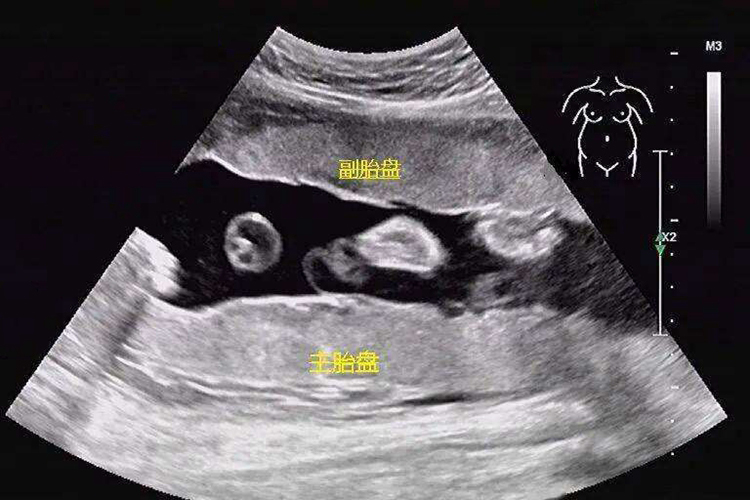

通过超声检查可发现副胎盘与主胎盘间多有血管相连,此血流束如横越宫颈内口,称胎盘血管前置,分娩时可发生致死性出血,所以超声检查副胎盘具有重要的临床意义。影像学检查中副胎盘呈扁圆形,其回声与主胎盘回声相同。